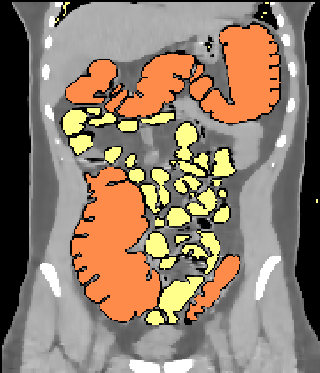

Mit Hilfe spezieller, dreidimensionaler Füllalgorithmen wird der luftgefüllte Darminnenraum automatisch markiert. Dick- und Dünndarm lassen sich ebenfalls automatisch trennen, sofern das Luftvolumen des Dickdarms nirgends kollabiert ist.

koronar_segment